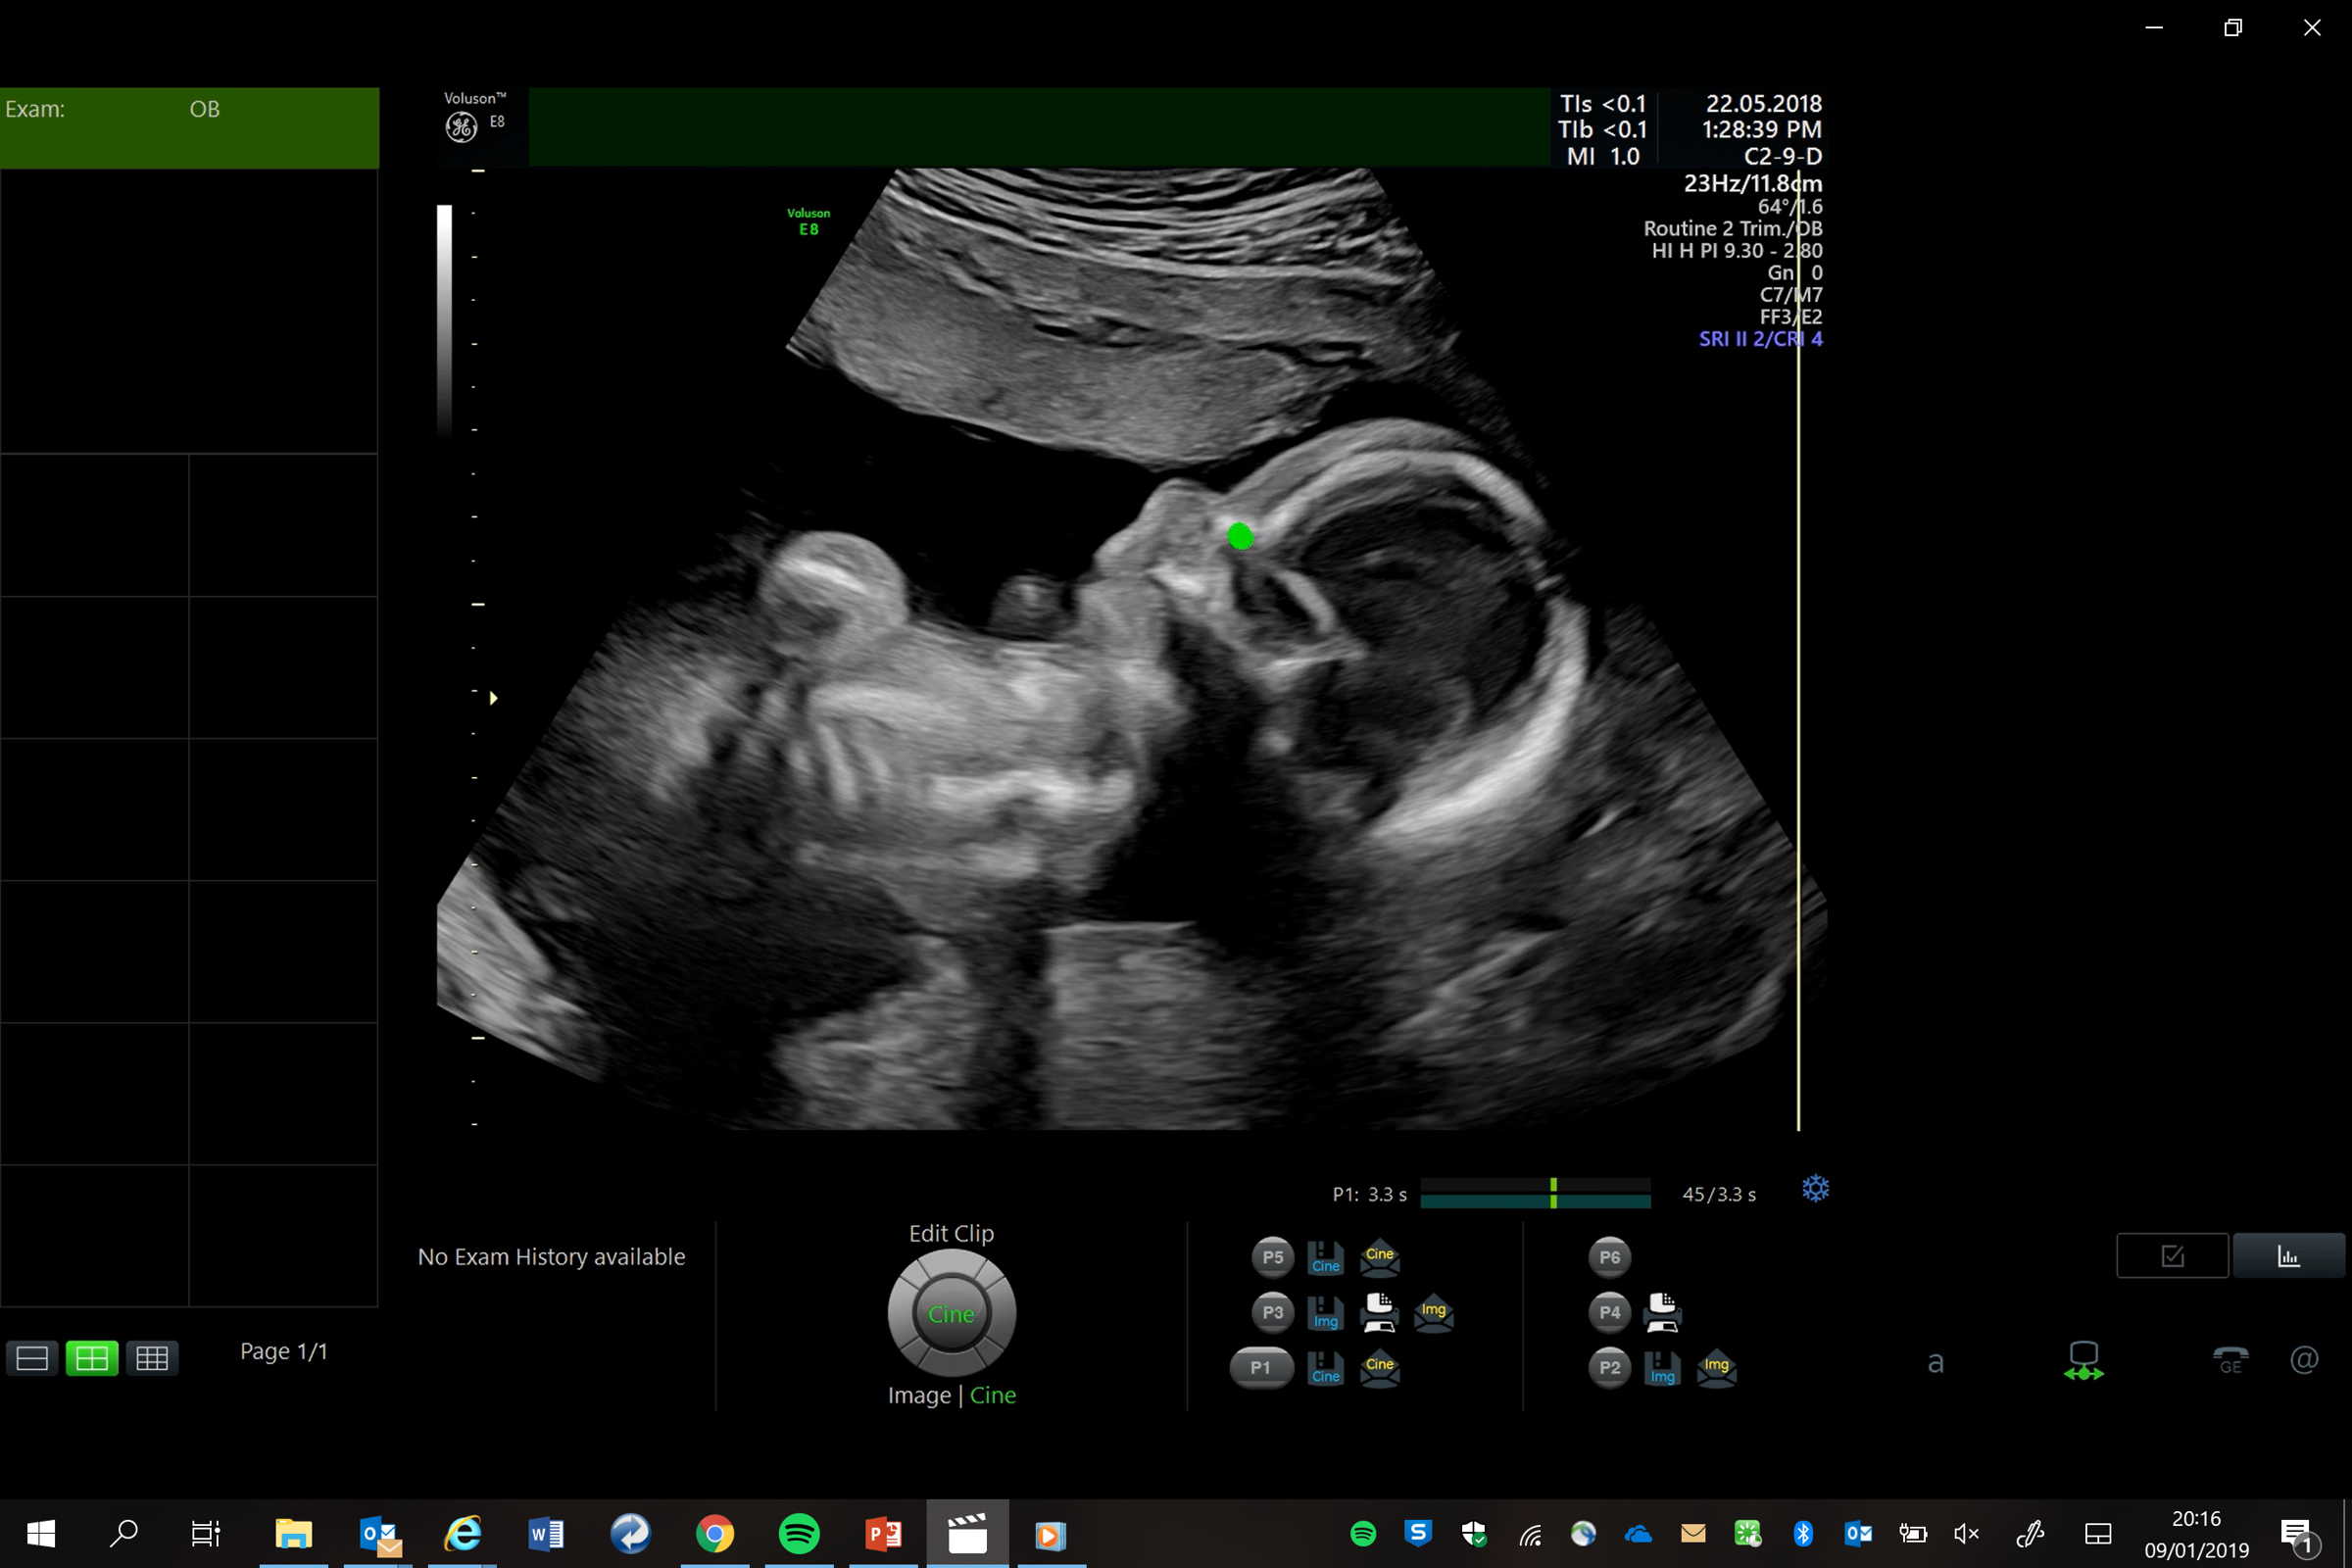

Perception Ultrasound by Learning Sonographic Experience

PULSE is an ambitious, innovative, interdisciplinary research project exploring the use of artificial intelligence-based technologies to reduce the need for highly trained ultrasound operators. We apply the latest ideas from machine learning and computer vision to build, from real-world ultrasound scanning videos, eye-tracking and probe movement data, computational models of visual search and navigation. These models describe how an expert sonographer performs a diagnostic study of a patient from multiple perceptual cues. By building models that more closely mimic how a human makes decisions from ultrasound images, we aim to demonstrate that we can build considerably more powerful assistive interpretation methods than have previously been possible from analysis of ultrasound images and videos alone.